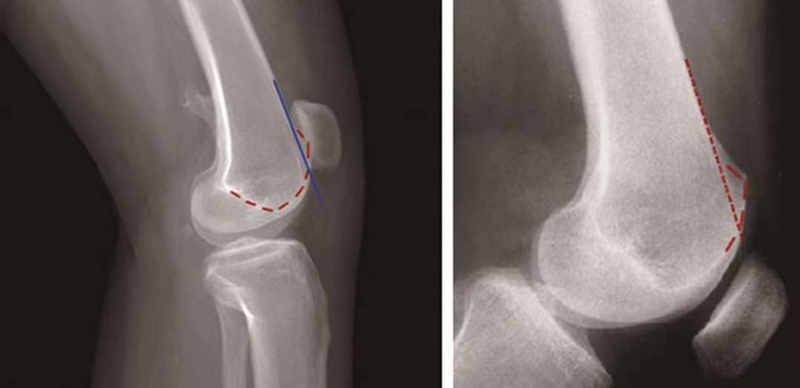

交叉征:

H.Dejour在1987年介绍了股骨滑车发育不良在膝关节标准侧位X线片的特殊表现,描述了交叉征(crossing sign)。在股骨滑车发育不良的膝关节标准侧位像上,股骨滑车沟基底线会与股骨外髁的轮廓线相交叉,即为交叉征(图11),意味着股骨滑车发育平坦。

图11 交叉征

突起征:

H.Dejour在1996年提出突起征(spur或bump)或滑车近端突起征(supratrochlear spur),是指在膝关节标准侧位像上,股骨滑车沟基底线的最高点位于股骨前方皮质延长线的前方(图12)。这种征象的实质是股骨滑车近端的整体抬高。在膝关节屈曲早期,髌骨必须越过滑车近端的突起才能进入股骨滑车,因此,容易出现髌骨向外脱位。如果突起征>5mm即为异常,意味着股骨滑车基底高于股骨外髁的轮廓。

图12 突起征

双轨征(或称为双线征):

是指在膝关节标准侧位像上,代表股骨内外侧滑车的两条线分开,呈双轨样(图13)。它的出现提示股骨内侧滑车发育低平,导致它的前缘出现晚于外侧滑车。

图13 双轨征